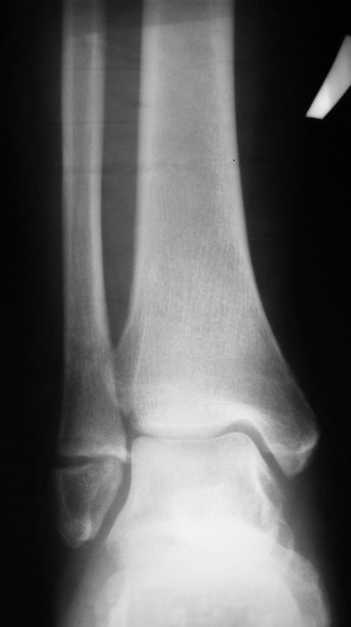

На одном из форумов заспорили о тактике.Женщина 23 года, рост 158, вес 55, профессия: менеджер, хобби: верховая езда, горные лыжи, велосипеды, не курит, сопутствующих заболеваний нет.28 июня упала с лошади.первый рентген:

Иммобилизация гипсовым сапожком до 20 августаНа сегодня- Гипс снаят, со слов больной "Наступать на ногу не больно, но страшно. Сустав и мышцы, конечно, плохо работают."

Вечер добрый! Судя по представленным рентгенограммам (с интервалом почти в два месяца!?) перелом не сросся. Лично я склоняюсь больше в сторону оперативного лечения (с учетом анамнеза пациентки). Но для принятия окончательного решения хотелось бы, для начала, увидеть снимки обоих суставов в сравнении в двух проекциях , а также сравнительные - фас под нагрузкой. При отсутствии жалоб со стороны пациентки на сегодняшний день (при данной рентгенологической картине), они (жалобы) ,скорее всего, появятся позже.

Ничего удивительного в том, что мнения хирургов разошлись нет, поскольку в целом в мире разные хирурги исповедуют разные тактики лечения переломов наружной лодыжки. Так одни считают, что нужно оперировать даже при смещении в 1 мм, другие допускают 5 мм. В среднем считают «цифрой старта» 2-3 мм. Но все сходятся в том, что нужно ориентироваться на функциональные запросы пациента. Но в вашем случае уже не свежий перелом, а замедленная консолидация со смещением отломков. (Delayed malunion? :-{)

Андрей, я всё таки склонен считать, что принципиального разногласия нет. На сегодняшний день рекомендовать оперативное лечение меня заставили следующие факторы:

1. Увеличивающийся диастаз фрагментов,

2. Отсутствие на рентгеновских снимках признаков образования костной мозоли, с одной стороны и

3. Образование кортикальной замыкательной пластинки на проксимальном фрагменте в зоне контакта, с другой,

1- Диастаз увеличивается. За счет чего? Сам дистальный отломок наружной лодыжки как был на месте, так и стоял. Т.е. увеличение диастаза не за счет подвижности и нестабильности, а за счет резорбции.

Данный перелом по классификации Вебера относится к типу А- т.е. дистальнее синдесмоза. В этом месте малоберцовая кость не несёт никакой нагрузки. Прошло только 2 месяца с момента перелома дайте больной что-то типа Air cast на месяц-полтора и полную нагрузку на ногу и сгибательно-разгибательные движения в суставе.